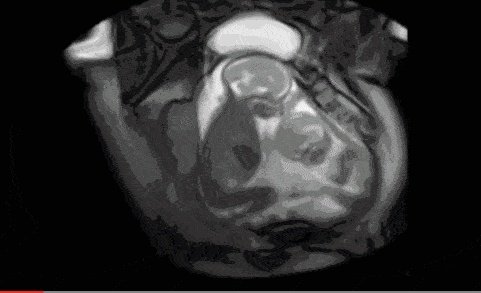

其实,双胞胎有所不同,从医学角度讲,共有三种形式存在。上图这样的属于单绒单羊双胞胎,在妈妈肚子里还是有一定危险性的。

3、单绒单羊双胞胎:有同一个受精卵,两个宝宝共用胎盘且无羊膜间隔。这种是很少见也是风险比较大的。也就是说,两个宝宝在同一个房间生活。他们难免会碰到、脐带绕颈等情况,发生宫内窘迫的可能性增加。

单绒单羊双胞胎风险大

两个宝宝都在一个房间,当然更危险一些,具体表现为,胎儿畸形率、早产、死亡率、生长受限的可能性增加。对母体来说,孕妈患有妊娠合并症的风险指数增加,且两个宝宝可能会因为争夺营养而打架。毕竟,他们是共用胎盘,且胎盘的储存量并不会太多,也增加了脐带绕颈的风险。

尤其是两个宝宝之间没有羊膜阻隔,在孕晚期由于胎儿体积大,活动起来更容易造成脐带绕颈、打结的现象,这样胎儿可能会因为血供中断,导致窒息、死亡。一般医生会建议在32~34周就及时终止妊娠,拖得越久,对孕妈和胎儿越不利。